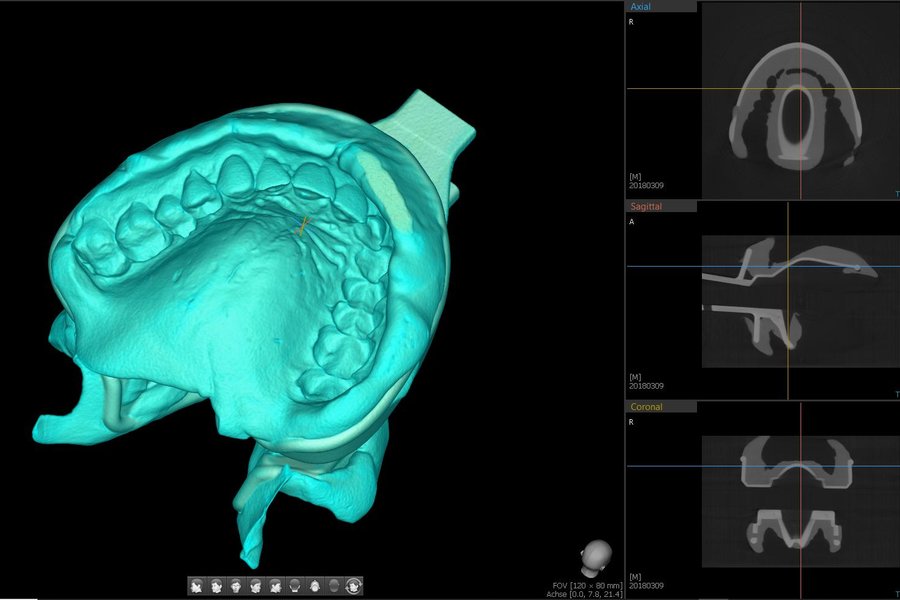

Das Green X ist ein 4-in-1 Röntgenbildgebungssystem der Superlative, welches sowohl 2D-Modalitäten wie Panorama- und kephalometrische Aufnahmen in ultrahochauflösender Bildqualität ermöglicht, als auch flexible 3D-DVT-Aufnahmen von Patienten, Modellen und Abformlöffeln.

• 4-in-1 Digital X-Ray Imaging System Pano / Ceph / DVT / Modellscan

• Multi-FOV-Auswahl für alle dentalen Indikationen 4x4 / 5x5 / 8x5 / 8x8 / 12x9 / 16x9

• Green DVT Low-Dose- und High-Resolution-Modus

• Endo Modus mit höchster Auflösung FOV 4x4; Ultra-High-Resolution 49µm; 3,5 Lp/mm

• Free FOV Insight PAN 2.0 Multilayer mit 41 Schichten

• 3D - Diagnose- und Planungssoftware byzzEz3D - i

Das Green X ist mit 49μm bei einem FOV von 4x4 cm das Gerät mit einem der weltweit höchsten Auflösungen und der daraus resultierenden Detailschärfe. Dank der byzzEz3D-i Software mit dem Endo-Modul rekonstruiert diese aus ultrahochauflösenden Schichtaufnahmen perfekte 3D Aufnahmen. Diese können dann als Hologramm in allen drei Dimensionen vermessen werden.

Ein ideales Instrument zur Vorbereitung für jede Wurzelkanalaufbereitung und WSR und auch ein hervorragendes Hilfsmittel zur 3D-Visualisierung, Behandlungsplanung und Patientenberatung.

Die Überlagerung der Oberflächenmodelle (STL-Daten) aus externen Scan-Systemen ist durch die exzellente Oberflächendarstellung der 3D-Röntgenaufnahmen problemlos und komfortabel. Somit bietet das Green X alle Möglichkeiten, den digitalen Workflow im Praxisalltag umzusetzen. Eines für alles und alles für Sie!

3D-Modell-Scan: Ready for CAD/CAM

Integrierter Laborscanner mit automatischer Datenspeicherung im byzznxt Langzeitarchiv

Die integrierte Modell-, Abdruck- und Prothesenscan-Funktion des Green X bietet die Möglichkeit, die zur Fertigung von Bohrschablohnen und Interims-Prothesen, notwendigen Daten zu erfassen. Mit der STL-Konvertierungsfunktion der byzzEz3D-i Software können jederzeit die gewünschten Daten im Standard STL-Format exportiert werden. Zusätzlich werden alle Scandaten im Langzeitarchiv von byzznxt abgespeichert und die Daten stehen somit jederzeit für 3D-Druck oder CAD/ CAM-Verfahren zur Verfügung.